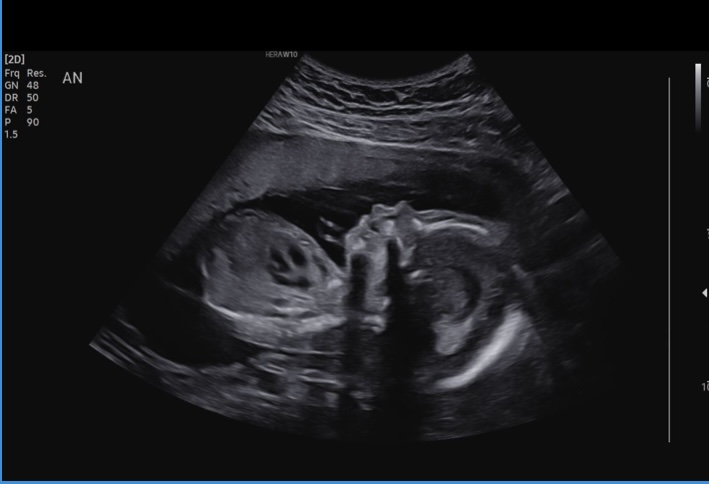

We had our halfway ultrasound and got to see our wiggly little guy! He was moving all over, but then refused to move when the tech needed him to so she could get a better angle. Such a stubborn little boy! Everything is measuring perfectly and all looks great, which is such a relief and we are so grateful! Little guy is moving a LOT now and I can feel him all the time, which makes it much more real that we’re actually having a baby!